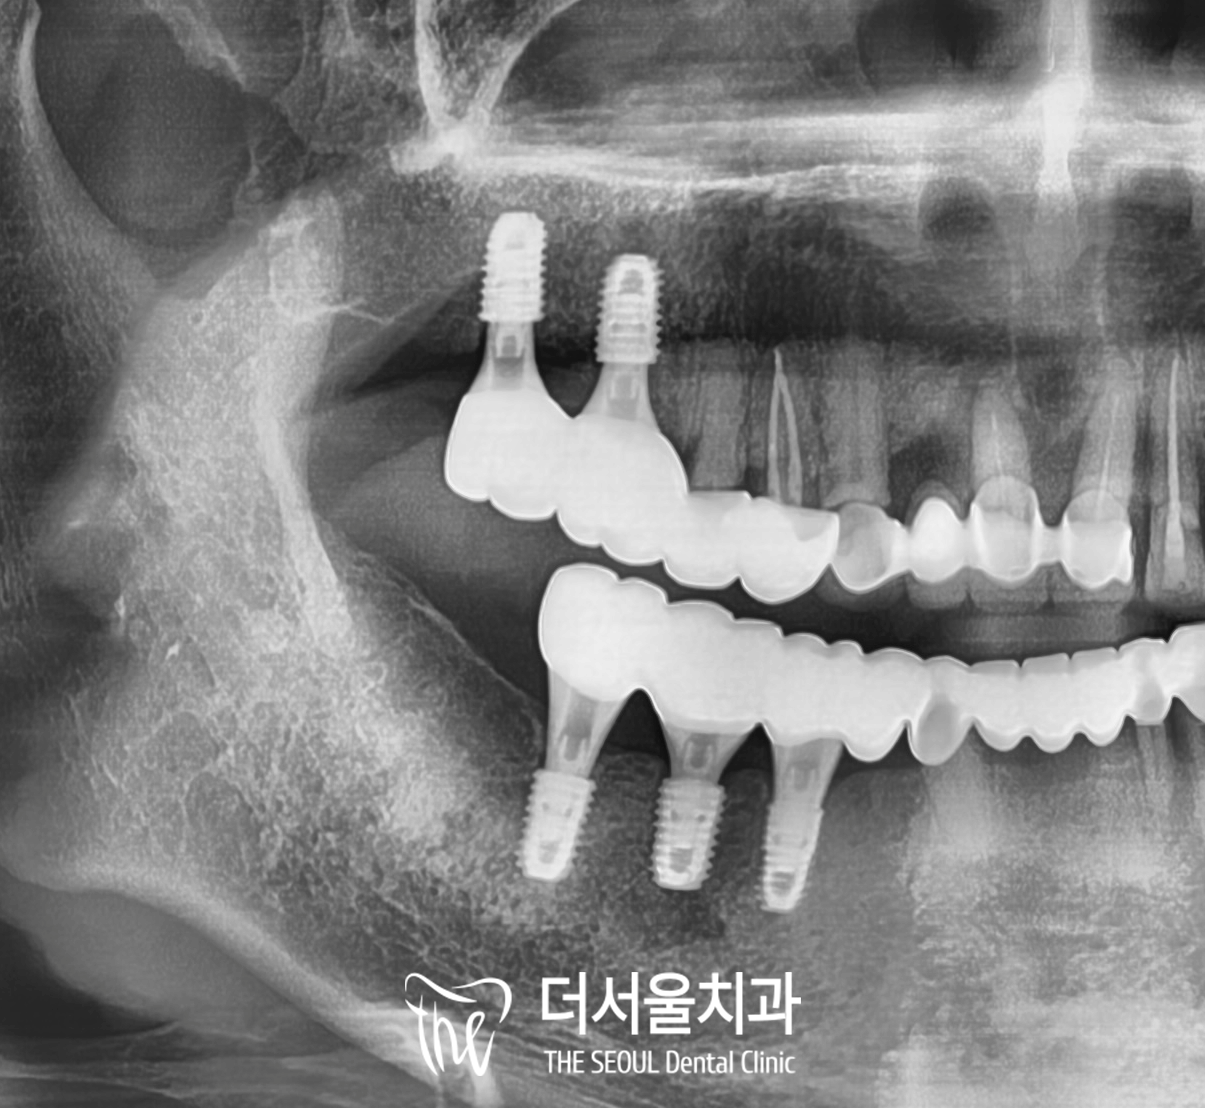

그리고 3개월 정도 뒤,

이번에는 픽스처와 치조골의

유착이 확인되면

위쪽에 임플란트 브릿지를

연결해 줍니다.

구치부는 저작력이 강하기에

크라운 두 개를 연결하여

그 힘을 분배할 수 있도록 해주었습니다.